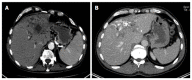

Aim: To establish a computed tomography (CT)-morphological classification for hepatic alveolar echinococcosis was the aim of the study.

Methods: The CT morphology of hepatic lesions in 228 patients with confirmed alveolar echinococcosis (AE) drawn from the Echinococcus Databank of the University Hospital of Ulm was reviewed retrospectively. For this reason, CT datasets of combined positron emission tomography (PET)-CT examinations were evaluated. The diagnosis of AE was made in patients with unequivocal seropositivity; positive histological findings following diagnostic puncture or partial resection of the liver; and/or findings typical for AE at either ultrasonography, CT, magnetic resonance imaging or PET-CT. The CT-morphological findings were grouped into the new classification scheme.

Results: Within the classification a lesion was dedicated to one out of five "primary morphologies" as well as to one out of six "patterns of calcification". "primary morphology" and "pattern of calcification" are primarily focussed on separately from each other and combined, whereas the "primary morphology" V is not further characterized by a "pattern of calcification". Based on the five primary morphologies, further descriptive sub-criteria were appended to types I-III. An analysis of the calcification pattern in relation to the primary morphology revealed the exclusive association of the central calcification with type IV primary morphology. Similarly, certain calcification patterns exhibited a clear predominance for other primary morphologies, which underscores the delimitation of the individual primary morphological types from each other. These relationships in terms of calcification patterns extend into the primary morphological sub-criteria, demonstrating the clear subordination of those criteria.

Conclusion: The proposed CT-morphological classification (EMUC-CT) is intended to facilitate the recognition and interpretation of lesions in hepatic alveolar echinococcosis. This could help to interpret different clinical courses better and shall assist in the context of scientific studies to improve the comparability of CT findings.